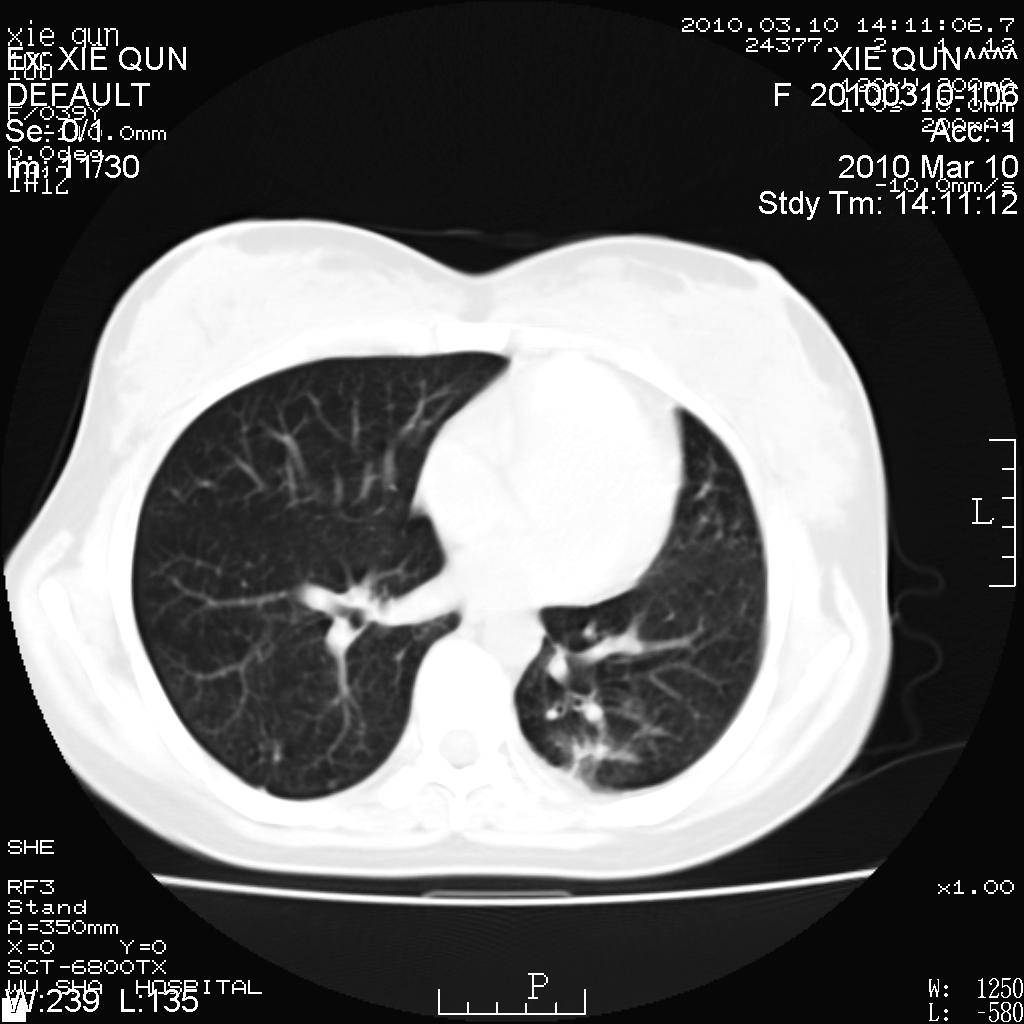

以下是引用心路寻觅在2010-3-24 17:28:00的发言:[br]两肺继发性tb左上肺空洞形成,建议痰检明确诊断。

以下是引用随光逐影在2010-3-24 19:19:00的发言:[br]两肺继发性结核并左上肺上叶空洞形成。